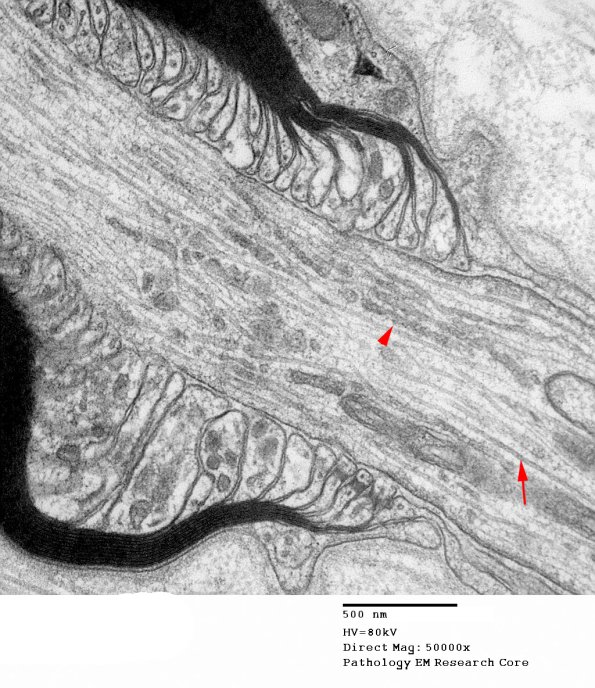

Washington University Experience | PERIPHERAL NEUROPATHY | 3 NORMAL MYELIN & SCHWANN CELLS | 2 Node of Ranvier | 11A5 Normal Node of Ranvier (Case 9) EM A_170 copy.jpg

In this section it is possible to see that paranodal loops contain subcellular organelles and the endoplasmic reticulum is present in long continuous sections (arrowhead) intercalated between microtubules (arrow).